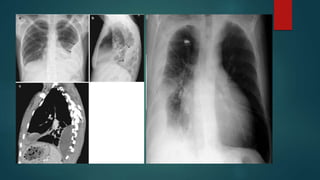

CXR

 Lateral decubitus* CXR requires at least 75 ml of fluid

 CXR PAV requires at least 150 ml of fluid to be detected

CXR  Lateral decubitus*CXR requires at least 75 ml of fluid  CXR PAV requires at least 150 ml of fluid to be detected  Supine CXR are fallacious to detect pleural effusion  CXR PA view d/ds Subpulmonic effusion Costophrenic and cardiophrenic recesses Blunting of hemidiaphragm Homogenous fluid dense radio-opacity in the lung field and making meniscsus without any bronchovascular markings within Large effusions causes underlying lung collapse and mediastenal shift to opposite side

Exceptionally on CXR Loculated pelural effusion and effsuions in fissures are non dependent  Parapneumonic effusions are difficult to be detected on CXR Grading of effusion on CXR  Mild - Up to causing CoP angle blunting  Moderate - In between  Massive - almost entire hemithorax opaque with collapsed lung